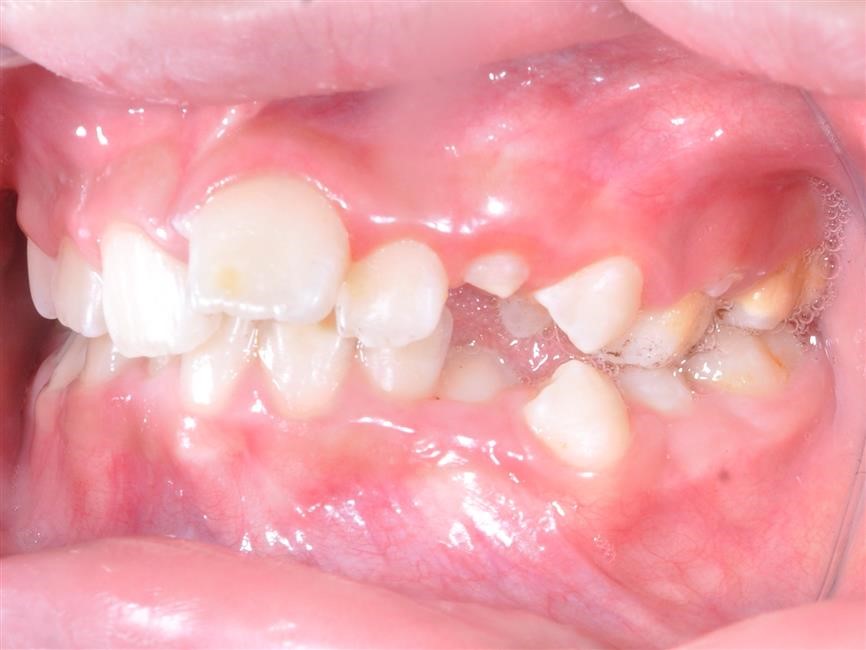

Vậy như thế nào là khớp cắn bình thường và khớp cắn lệch lạc? Đáng ngạc nhiên là không chỉ đơn thuần có một câu trả lời. Một khớp cắn bình thường được mô tả bằng những tiêu chí như: lý tưởng, phù hợp giải phẫu, mang tính trung bình, mang tính thẩm mỹ, hợp lý, đảm bảo chức năng cắn và khớp cắn không ảnh hưởng tới sức khỏe răng miệng. Do vậy, trên thực tế, cùng một vấn đề nhưng có thể có tồn tại nhiều hướng giải quyết khác nhau: điều trị hay không điều trị. Lệch lạc khớp cắn không phải là một bệnh nhưng là một biến thể khác so với tình trạng bình thường và có thể ảnh hưởng không tốt đến tình trạng sức khỏe răng miệng nói chung. Về cơ bản, có ba nguyên nhân chính dẫn tới việc cần phải tiến hành chỉnh nha: 1- Tình trạng, khấp khểnh, vẩu răng-hàm 2- Điều chỉnh chức năng ăn nhai của răng 3- Loại bỏ các nguy cơ có thể gây tổn hại tới sự khỏe mạnh lâu dài của răng và mô quanh răng.

Chức năng cắn: Những răng không được tiếp xúc tốt với răng tương ứng ở hàm đối diện có thể gây khó khăn khi ăn uống và có thể dẫn tới rối loạn chức năng khớp thái dương- hàm. Tuy nhiên, mối liên hệ giữa rối loạn chức năng khớp thái dương hàm và lệch lạc khớp cắn vẫn là một vấn đề gây tranh cãi. Những cá nhân có khớp cắn không tốt, có thể cảm thấy khó khăn và ngượng ngùng khi ăn vì họ không thể cắn được miếng thức ăn bằng răng cửa của mình. Họ chỉ có thể nhai thức ăn bằng những răng phía sau. Sức khỏe răng miệng: Vệ sinh răng miệng trở nên khó khăn hơn. răng dễ có mảng bám và cao răng hơn nếu hàm răng khấp khểnh không đều. Do vậy, bệnh nhân có thể dễ bị sâu răng và các bệnh nha chu khác như viêm lợi và viêm quanh răng hơn. Tuy nhiên, nếu có một hàm răng đều đặn mà không có ý thức và thực hành vệ sinh răng miệng tốt thì cũng không thể có tình trạng vệ sinh răng miệng tốt. Nếu chải răng không đầy đủ và không đúng cách, các bệnh nha chu sẽ tiến triển bất chấp hàm răng của họ thẳng đều đến mức nào. Trong nhiều trường hợp lệch lạc khớp cắn có thể làm tổn thương cả răng và mô mềm nếu không được điều trị. Hiển nhiên rằng răng cửa hàm trên càng chìa ra nhiều bao nhiêu thì nó lại càng dễ bị tổn thương bấy nhiêu. Khi khoảng cách theo chiều ngang giữa răng cửa hàm trên và răng cửa hàm dưới là 9mm hoặc lớn hơn, nguy cơ tổn thương răng cửa hàm trên tăng lên tới hơn 40%. Giảm độ chìa ra của răng cửa hàm trên không chỉ có lợi ích trên quan điểm thẩm mỹ mà còn hạn chế tối đa nguy cơ chấn thương và sự phức tạp về lâu về dài cho cả hàm răng. Những tình trạng khớp cắn ngược, không chỉ ảnh hưởng nhiều đến vấn đề thẩm mỹ mà còn ảnh hưởng đến chức năng cắn và gây ra tình trạng mòn răng – răng sớm, răng cửa dưới bị tiêu xương ổ răng, lợi bị co…Trong trường hợp được điều trị sớm, tổn thương mô mềm sẽ dừng lại và khi phần lợi còn lại được tái tạo thì tình trạng sẽ được cải thiện một cách tự nhiên và không để lại vấn đề gì sau này.

Khớp cắn chéo quá sâu có thể tình cờ gây ra loét mô mềm, những trường hợp này nhu cầu thẩm mỹ thì nhỏ nhưng vấn đề loại bỏ nguyên nhân gây chấn thương mô mềm thì lớn. Ai nên được điều trị chỉnh nha? Phần lớn điều trị chỉnh nha được tiến hành vì nhu cầu thẩm mỹ và lợi ích mà mỗi bệnh nhân nhận được từ việc điều trị sẽ phụ thuộc vào mức độ trầm trọng của mức độ sai khớp cắn và nhận thức của bệnh nhân về vấn đề này. Một số cá nhân có thể có sự lệch lạc ở mức độ quá rõ ràng làm ảnh hưởng trầm trọng tới gương mặt của họ tuy nhiên họ cũng chẳng quan tâm đến và không cần điều trị nếu bác sỹ không có cách thuyết phục. Bác sĩ lâm sàng có thể đưa ra lời khuyên về phương pháp điều trị cho bệnh nhân nhưng cũng không nên yêu cầu họ một cách cứng nhắc mà nên để cho họ có thời gian ngồi lại và suy nghĩ để đưa ra quyết định cuối cùng hợp tác với bác sỹ điều trị. Lệch lạc khớp cắn mức độ nhẹ nên được điều trị với sự cẩn trọng vì khả năng tái phát sau khi điều trị. Các bậc phụ huynh có thể có rất nhiều yêu cầu khác nhau nhưng các bác sĩ lâm sàng nên tiếp cận những vấn đề này một cách cẩn trọng và chỉ tiến hành điều trị khi nó đem lại lợi ích tốt nhất cho bệnh nhân. Điều thiết yếu nhất cần nhớ là phụ huynh và bác sĩ cần phải nhận thức rõ về những hạn chế cũng như sự đòi hỏi nhiều thời gian của việc điều trị chỉnh nha. Kế hoạch điều trị nắn chỉnh răng Trong quá trình phát triển của bộ răng người, có thể chia làm ba giai đoạn chính như sau: giai đoạn răng sữa, giai đoạn răng hỗn hợp và giai đoạn răng vĩnh viễn. Sau đây là một số gợi ý những trường hợp nào cần và nên điều trị theo các giai đoạn của bộ răng: Kế hoạch điều trị ở hàm răng sữa Lý do điều trị: điều trị nắn chỉnh răng ở hàm răng sữa vì lý do sau: (1) loại bỏ các cản trở đến sự tăng trưởng bình thường của mặt và cung răng. (2) duy trì hoặc phục hồi lại chức năng bình thường Các trường hợp cần phải điều trị: a) Cắn chéo phía trước và sau.